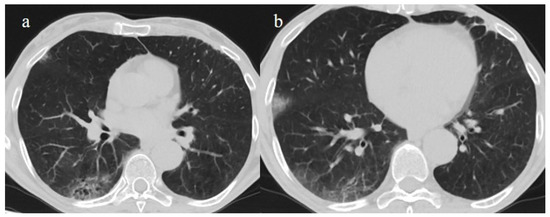

3.3.4. Pulmonary Thromboembolism

| Typical Appearance | GGOs with a crazy-paving pattern and consolidations in a peripheral and posterior or central-peripheral distribution; multilobar involvement; vascular enlargement, the halo and reversed halo sign; subpleural and parenchymal bands; and architectural distortion. They were predominant since the Delta wave. |